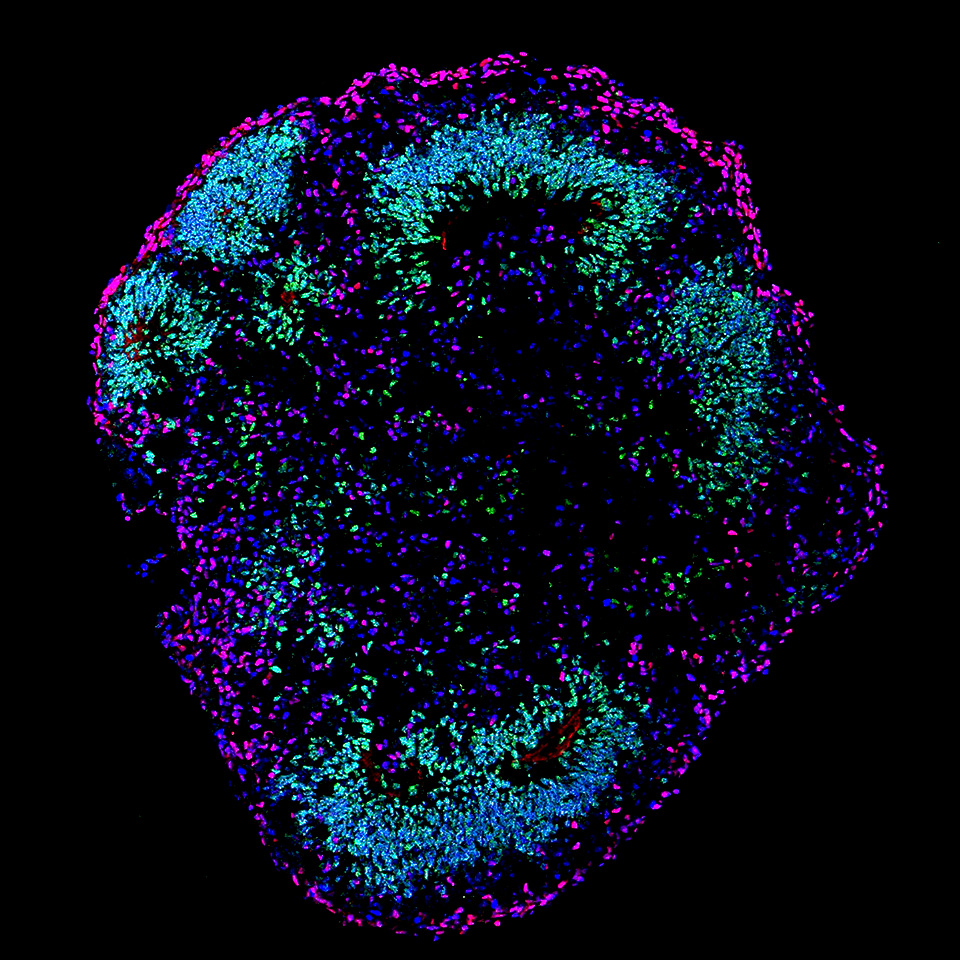

研究対象とする最先端技術の一つがオルガノイド技術。培養皿でiPS細胞など多能性幹細胞から作られる3次元の組織はオルガノイドと呼ばれ、神経領域では大脳、小脳、海馬、中脳、視床、脊髄など、その他の臓器では腎臓、肝臓、胃、腸などの作製に成功している。

生体内と同じ構造を持つ組織を体外で再現できるため、疾患が発症する仕組みの解明や創薬への応用が期待される。「技術そのものはもちろん、その倫理的検討も前例がなくフロンティア。自分たちで未来を描いて議論するしかありません」。

ヒトの脳のように意識を持つ可能性があると言われる大脳オルガノイド。しかし実際は、脳の局所的な構造を豆粒ほどの大きさで再現できているのが現状だ。澤井助教は、大脳オルガノイドが意識を持つと推定するのはやや尚早とした上で、意識を持つことをただ問題視するのではなく、どのような意識を持つかを議論することが重要だと考える。「最先端であるほど得られる情報は少ない。技術そのものを正しく把握することすら難しく、議論が飛躍しがちです。でもASHBiやCiRAでは、最前線でその技術を開発・応用している科学者たちと直接意見を交わすことができます。正確な情報に基づいて議論しなければ、過度に規制してしまうだけでなく、規制すべきところを見逃す可能性もある。偏った情報に囚われてフィルターのかかった議論をしないよう心がけています」。

左と中央は培養37日の大脳オルガノイド。右は培養52日。生体で作られる脳の層構造が脳オルガノイドでも同様に再現され、培養37日に比べて培養52日のオルガノイドでは、より成熟した層構造を形成している(写真提供・坂口秀哉氏〈理化学研究所〉)